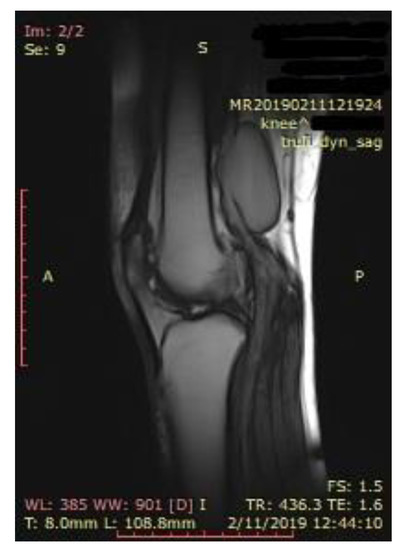

Two-point compression ultrasonography showed no signs of deep vein thrombosis. However, a complete ultrasonography of the lower extremity venous system in real-time B-mode revealed a 6 × 5 × 4 cm anechoic mass located in the cranial extremity of the left popliteal fossa, contiguous to the popliteal vein, with sluggish, swirling blood flow, but no signs of thrombosis (Figure 1).

Figure 1.

Proximal left popliteal vein transverse axis view demonstrates a simple saccular dilatation, with partial thrombosis. The dotted lines represent the PVA’s dimensions.

Doppler spectral analysis revealed low velocity blood flow with normal phasic variation corresponding to a venous waveform.